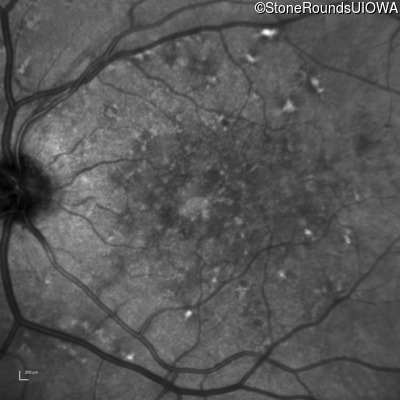

Fluorescein Angiography - Left - 20/20

Exemplar